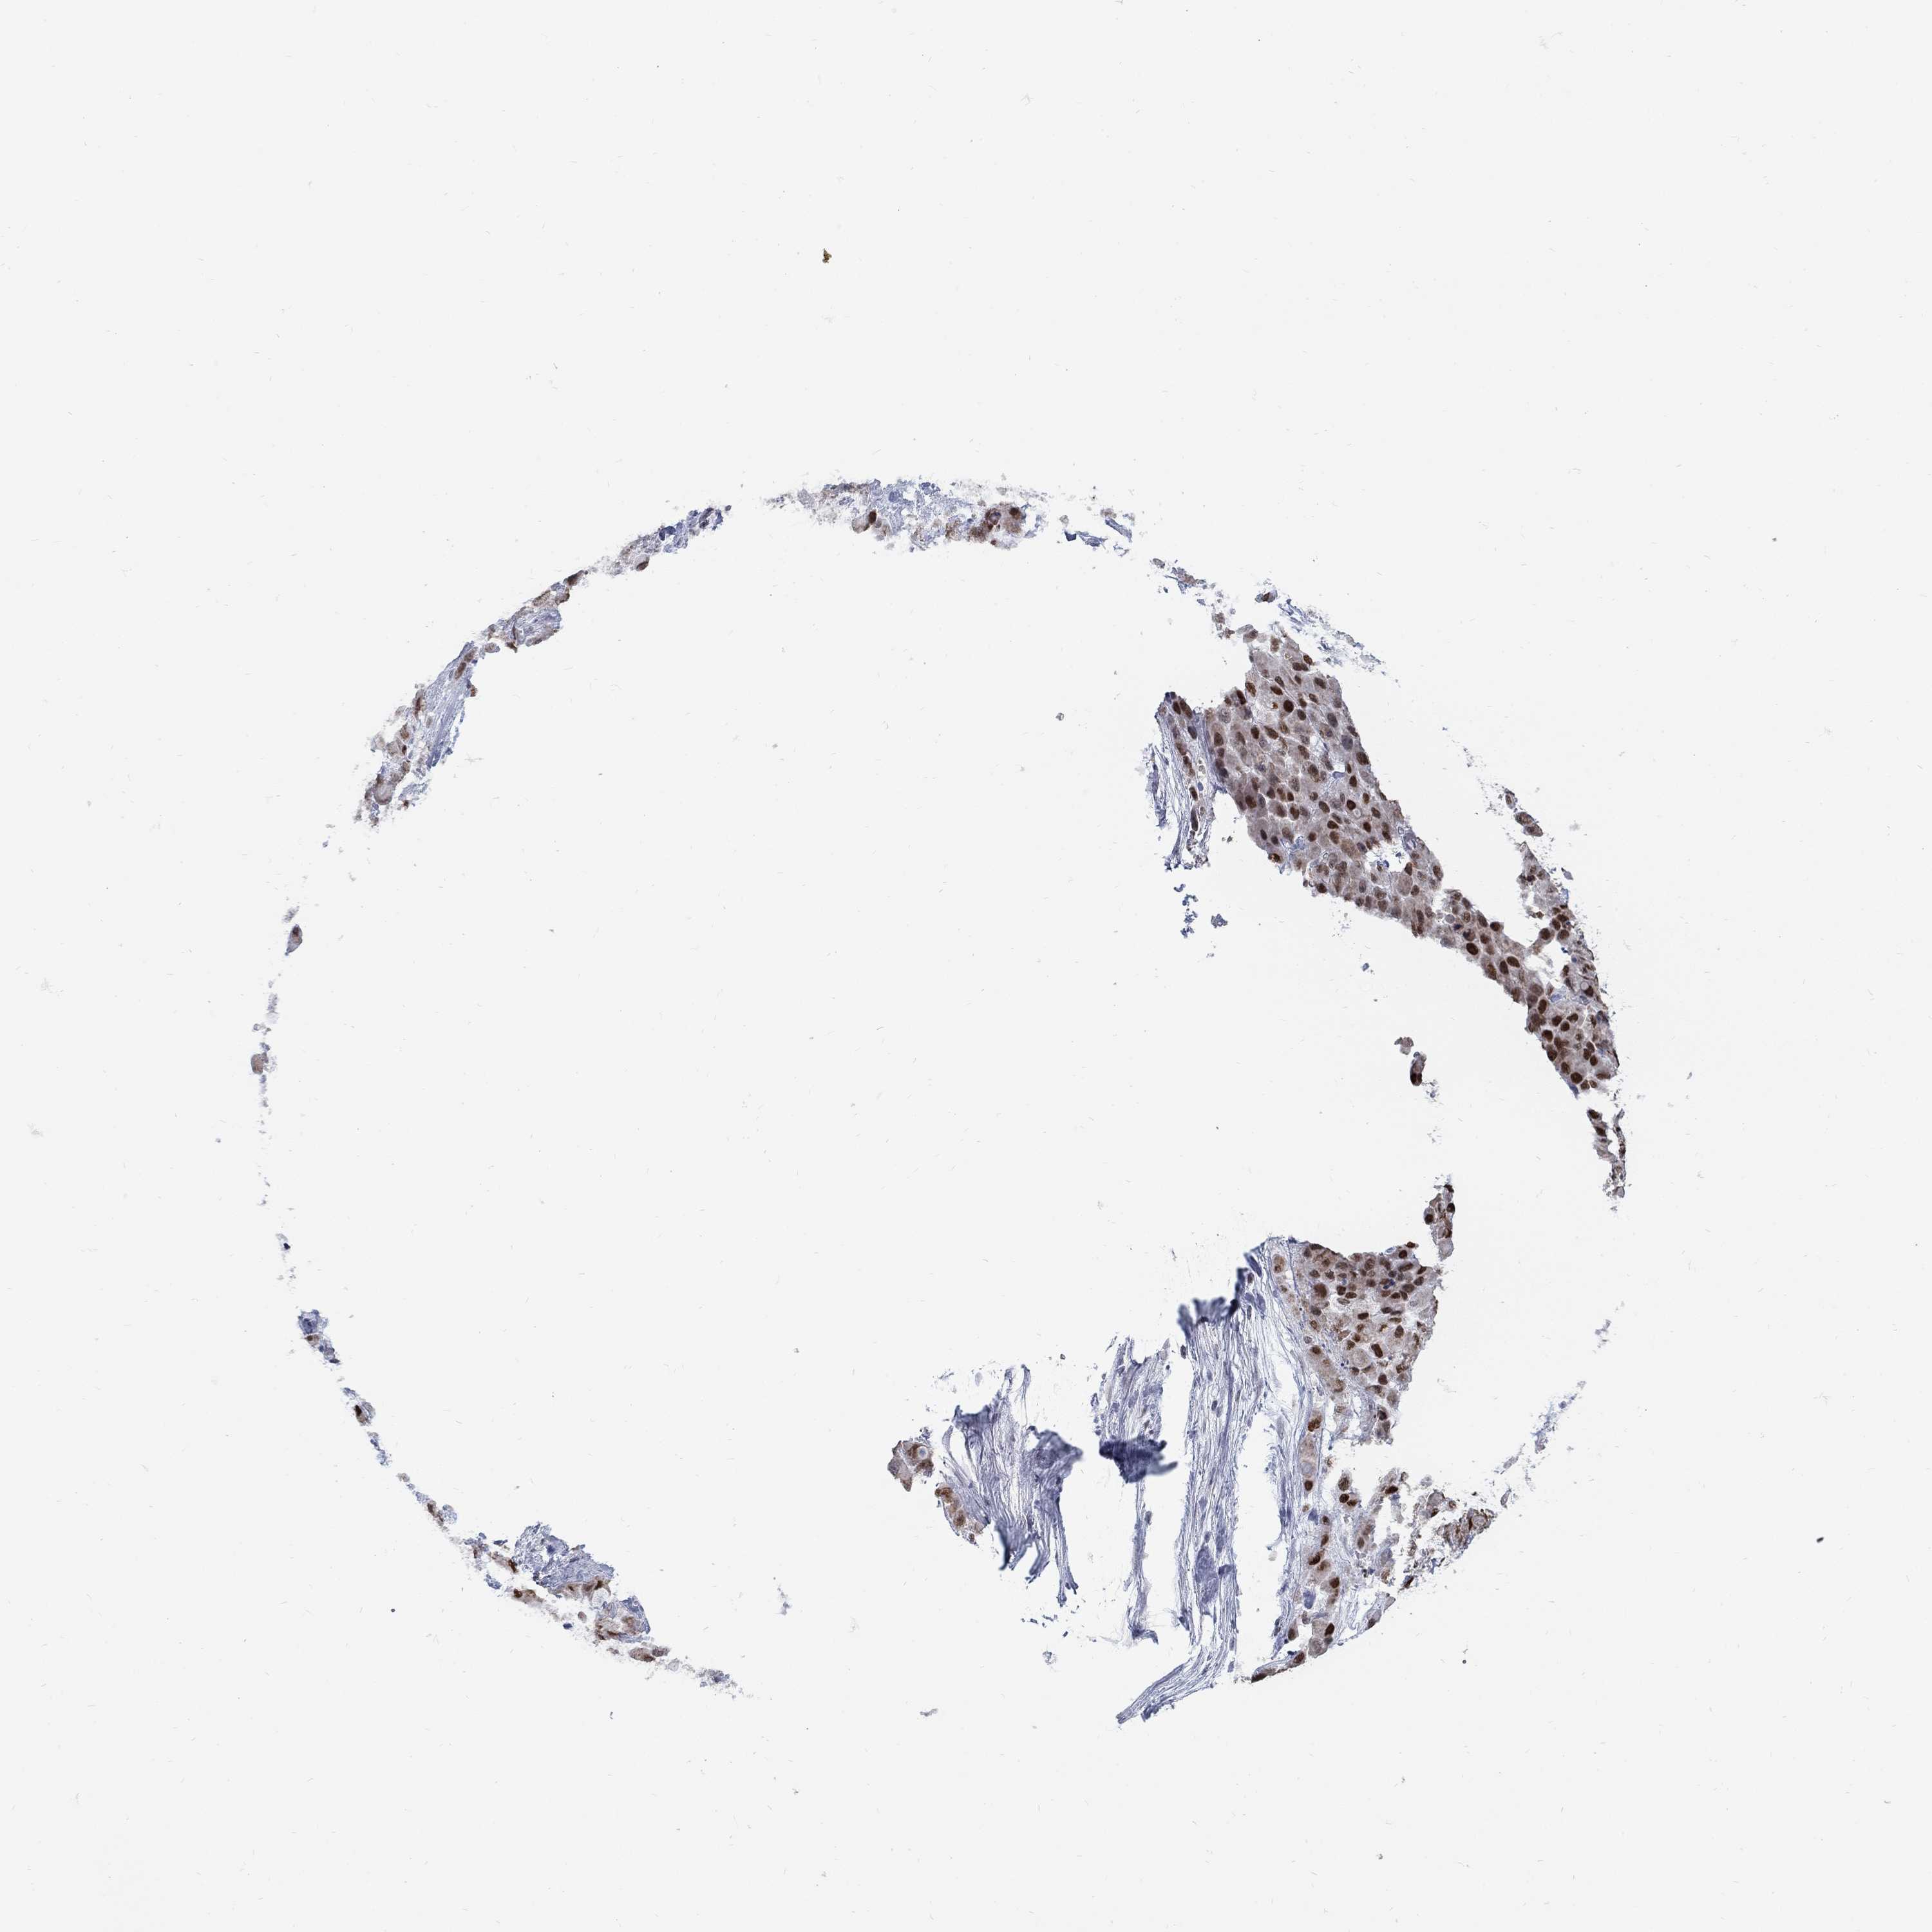

STOMACH CANCER - Protein expressioni

A mouse-over function shows sample information and annotation data. Click on an image to view it in a full screen mode. Samples can be filtered based on level of antibody staining by selecting one or several of the following categories: high, medium, low and not detected. The assay and annotation is described here.

Note that samples used for immunohistochemistry by the Human Protein Atlas do not correspond to samples in the TCGA dataset.

Antibody stainingi

Antibody staining in the annotated cell types in the current human tissue is reported as not detected, low, medium, or high, based on conventional immunohistochemistry profiling in selected tissues. This score is based on the combination of the staining intensity and fraction of stained cells.

Each image is clickable and will lead to virtual microscopy that enables deeper exploration of all samples and also displays staining intensity scores, fraction scores and subcellular localization as well as patient and tissue information for each sample.

Antibody HPA077882

Staining

High

Medium

Low

Not detected

Intensity

Strong

Moderate

Weak

Negative

Quantity

>75%

75%-25%

<25%

None

Location

Nuclear

Cytoplasmic/membranous

Cytoplasmic/membranous,nuclear

Adenocarcinoma, NOS